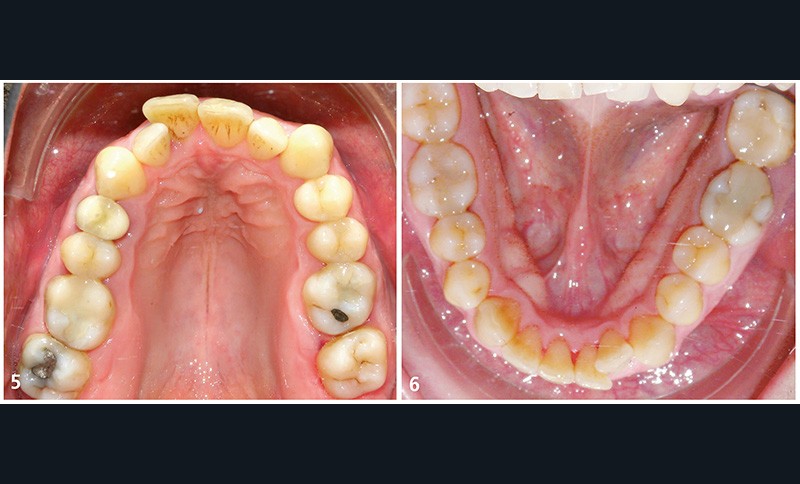

Il présente une malocclusion de classe II subdivison gauche totale par mésioposition du secteur 2 avec une déviation dentaire du milieu maxillaire à droite (fig. 2 à 6) dans un visage équilibré (fig. 7 et 8).

La mésioposition du secteur 2 a entraîné un encombrement antérieur avec malpositions des incisives supérieures, la 12 étant en occlusion traumatogène, en bout à bout avec son antagoniste (fig. 3). Dans le sens transversal, il existe une endoalvéolie maxillaire avec occlusion inversée postérieure à gauche. À l’arcade mandibulaire, l’encombrement est modéré (fig. 6).